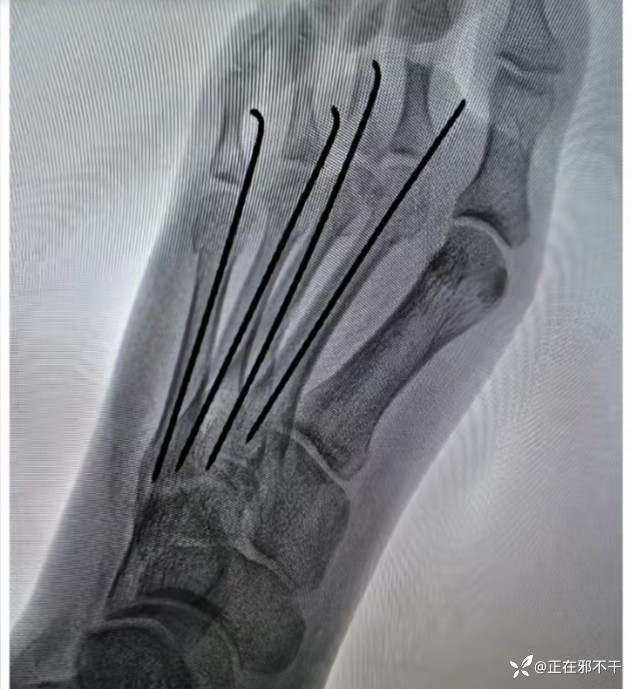

【治疗经过及结果】:给予克氏针闭合复位内固定

这种固定看似简单,做起来是需要技术的。

借助C型臂X射线机的监视与诱导,能够实现精确的解剖复位。此手术方式微创且无手术切口,从而显著减少甚至规避患者并发感染的风险。其稳定性亦相当出色,能够有效预防医源性的神经损伤,进而降低并发症的发生率。更为重要的是,它还能加速骨折的愈合进程,为患者节省医疗费用。